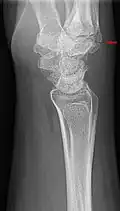

Additional images

Carpal boss in plain X-Ray. -